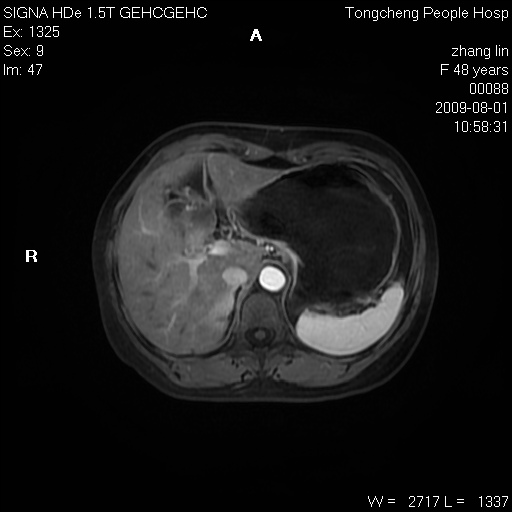

女,48岁。健康体检,彩超发现右肾占位性病变。平素健康。

临床诊断:右肾占位性病变,性质待定(囊肿?肿瘤?)。

上中腹部mr平扫+增强扫描,图像如下:

右肾上极见一类圆形病灶,t1wi呈等信号t2wi呈等高混杂信号,三期增强无强化,边界清---考虑囊肿出血。

同反相位均表现为等信号,病变无强化,考虑含蛋白的囊肿可能,弥散加权相或许有些帮助,